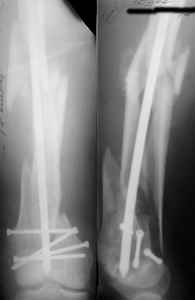

I presented a series of ~25 such cases at EuroTrauma'2004. Many cases were discussed here. I attach am example. Look also recent cases at http://www.hwbf.org/hwb/conf/alex58/scfx.htm,

KEMMD> Malpositioning is much too common (recurvatum, varus - valgus).

Did you mark valgus malalignment in that case with LISS you posted Nov 9? Aplication of external distractor can help to avoid the pitfalls but some further development of the technology is necessary to shorten the learning curve.